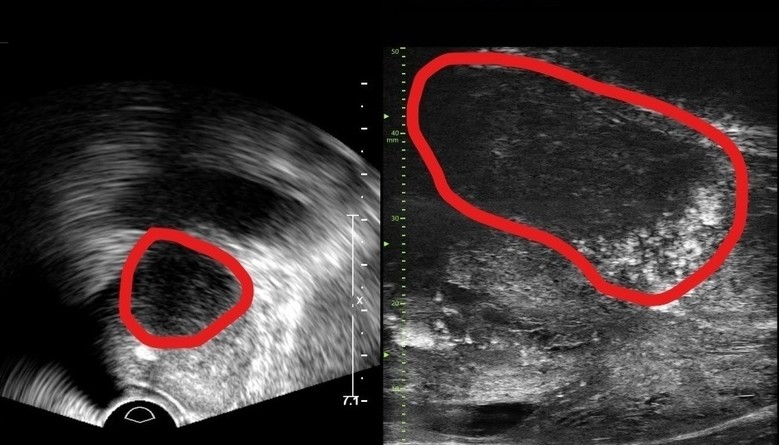

| ▲기존 전립선 초음파 사진(좌) 및 마이크로 초음파 사진(우). 기존 초음파는 전립선 부위(동그라미 친 부분)의 음영 차이로만 병변을 확인했지만, 마이크로 초음파는 높은 해상도를 통해 종양과 주변 조직의 모양까지 확인가능하다.(사진=분당서울대병원) |

29MHz 마이크로 초음파를 사용하는 이 장비는 전립선과 주변의 해부학적 구조를 선명히 표시하고 표적 조직검사를 유도한다. 의심 영역을 실시간으로 확인하면서 전립선 조직의 미세한 변화와 병변을 식별하고 조직검사 채취를 위한 바늘을 정확한 위치에 삽입할 수 있다는 장점이 있다.

기존의 경직장 초음파는 해상도가 낮아 전립선 종양, 특히 작은 암 병변을 감지하는 데 한계가 있었다. 하지만 마이크로 초음파의 높은 해상도와 실시간 영상의 시각화는 자기공명영상(MRI)으로 발견할 수 없는 전립선암을 찾을 때도 충분히 기여할 것으로 기대하고 있다. MRI 검사 보다 환자의 신체적, 심리적, 경제적 부담도 적을 수밖에 없다.